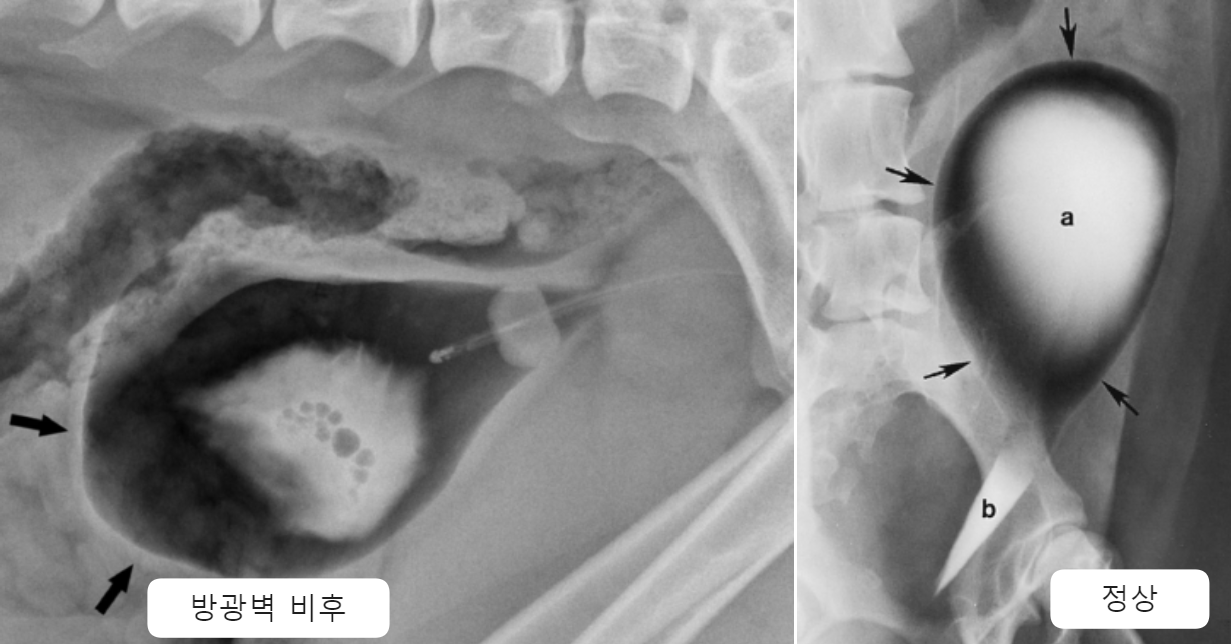

| - cycstitis (방광염) | - 작고, 빈 방광 / 방광벽 비후 (*드물게 결석, 종양 등으로 방광 비대) - caudal abdominal or lumpar pain |

| Radiographs _Cystitis | |

|---|---|

| - 작은 크기의 방광 - 방광벽의 비후(thickening), irregularity |

| Ultrasonography (Abd) _Cystitis | |

|---|---|

| - 방광벽 비후, 우둘투둘(∵종양, polyp) - 방광 내강의 Echogenic sediment  + Cystocopy(방광내시경) : 요도 → 방광 내부 감염 확률 존재 |

| Emphysematous cystitis (기종성 방광염)  | - Complicatted UTI, 당뇨 환자에서 종종 발병 - gas-producing bacteria가 방광 벽&내강에 gas accumulation - E. coli, Clostridium 등 - DM 환자에서 33, 신경 질환 환자에서 26%, 부신 질환 환자에서 19% 발생 |